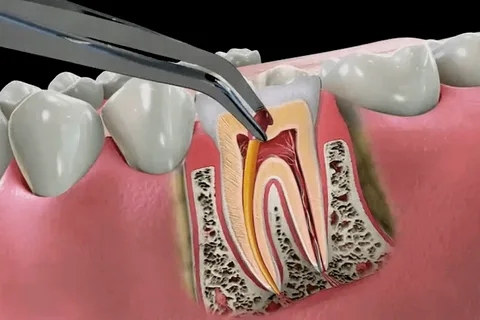

- Pulpektomija: Napravi se otvor u kruni zuba. Bolesna ili mrtva pulpa se uklanja iz pulpne komore i korijenskih kanala.

- Čišćenje i oblikovanje: Male turpije se koriste za čišćenje, proširenje i oblikovanje kanala kako bi se pripremili za punjenje.